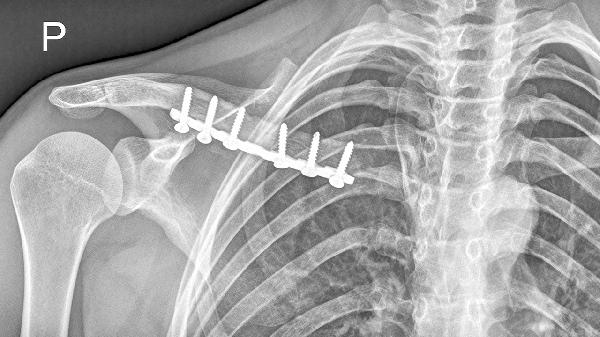

骨折部位在愈合期后仍存在异常活动,触诊可感知骨端不稳定。这与内固定失效、骨吸收或机械应力过大有关。治疗需重新评估固定稳定性,可能需更换内固定器材或辅以外固定支架。

X线或CT显示骨折线持续存在、骨痂形成不足、内固定松动或断裂。影像学是确诊骨不连的金标准,可明确骨缺损范围和愈合阶段。根据结果选择保守观察、体外冲击波或再次手术治疗。